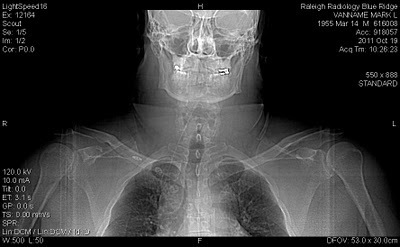

It's pretty cool stuff. Here's the first shot, my head straight on.

Do I look like the Terminator, or what?

Yeah, yeah, go ahead and say it: damn, that's a big neck. Yes, it is.